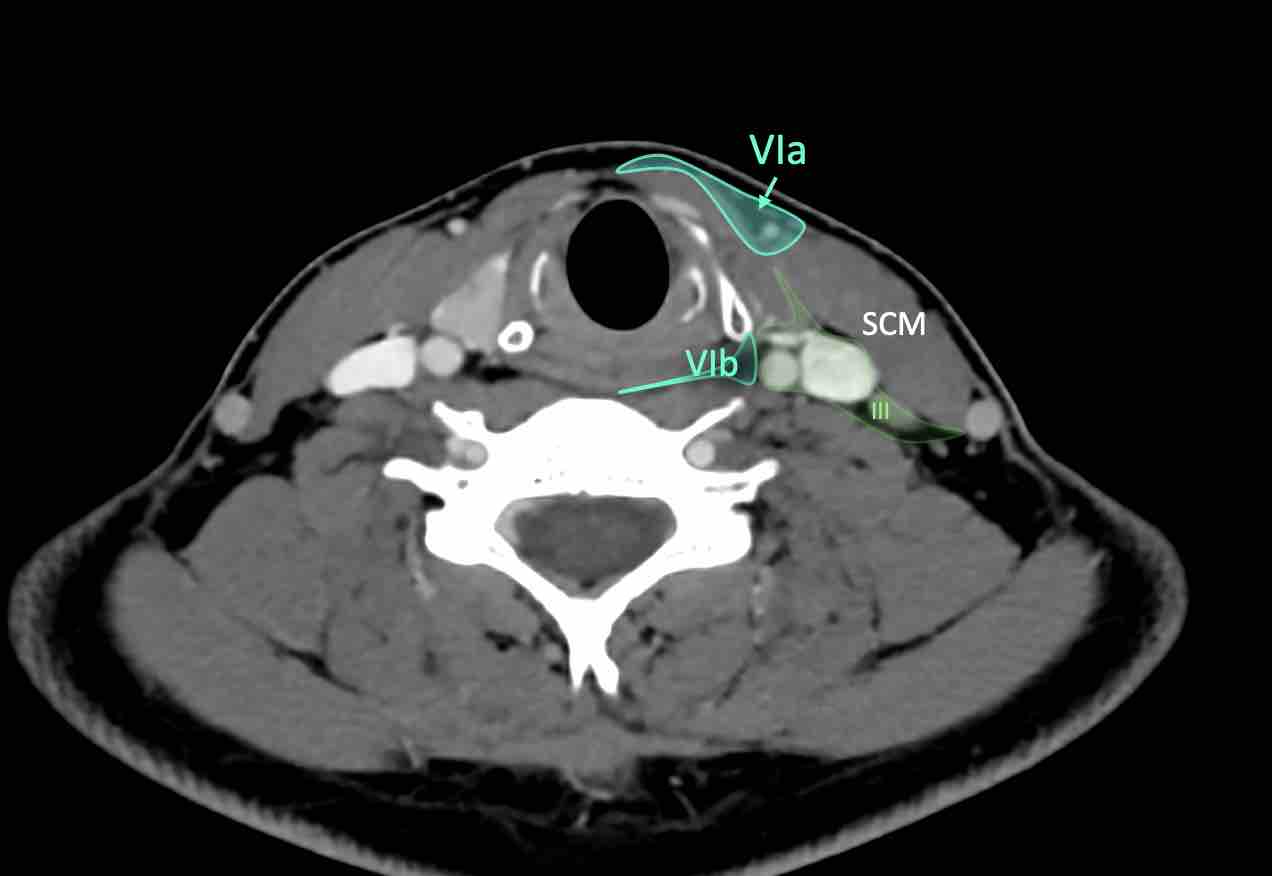

VI – Cổ trước

Tầng này chứa các hạch tĩnh mạch cảnh trước nông (tầng VIa) và các hạch sâu hơn bao gồm hạch trước thanh quản, trước khí quản, cạnh khí quản và hạch thần kinh thanh quản quặt ngược (tầng VIb).